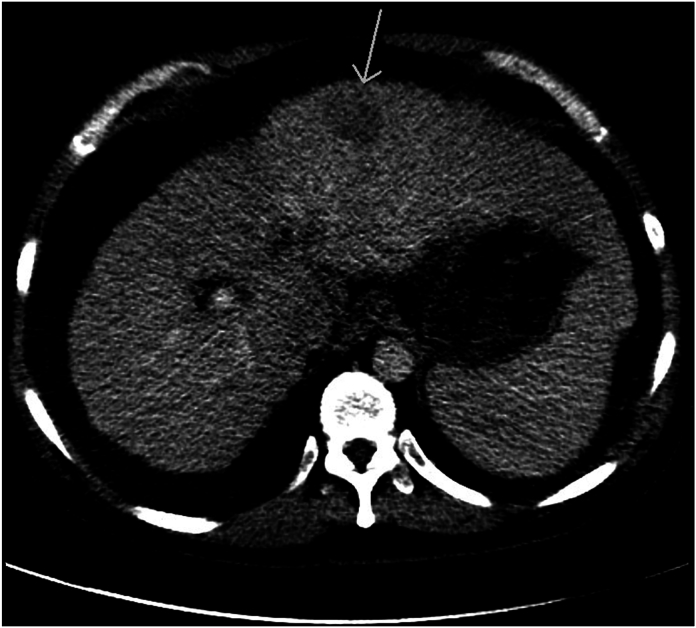

As part of the initial workup, a CT scan is obtained (Fig. 1, Fig. 2, Fig. 3).

Fig. 1.

HCC CT1

Axial post contrast CT demonstrates a hypodense left hepatic lobe mass (arrow) as well as cirrhotic liver morphology with a micronodular capsular contour.

The CT scan demonstrates a hypodense left hepatic lobe mass within a cirrhotic liver with a micronodular capsular contour. Given the prevalence of hepatocellular carcinoma in the cirrhotic patient population, this mass should be viewed as suspicious for HCC until proven otherwise.